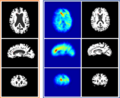

- Project week (Boston, 2010): We have 1) extended HAMMER registration algorithm to work on intensity image, bypassing the pre-segment of MR images; 2) replacing the gaussian propagation with the thin-plate interpolation to achieve more accurate and efficient registration; 3) implement the soft-assignment strategy, instead of the one-to-one correspondence, in detecting correspondence during registration.